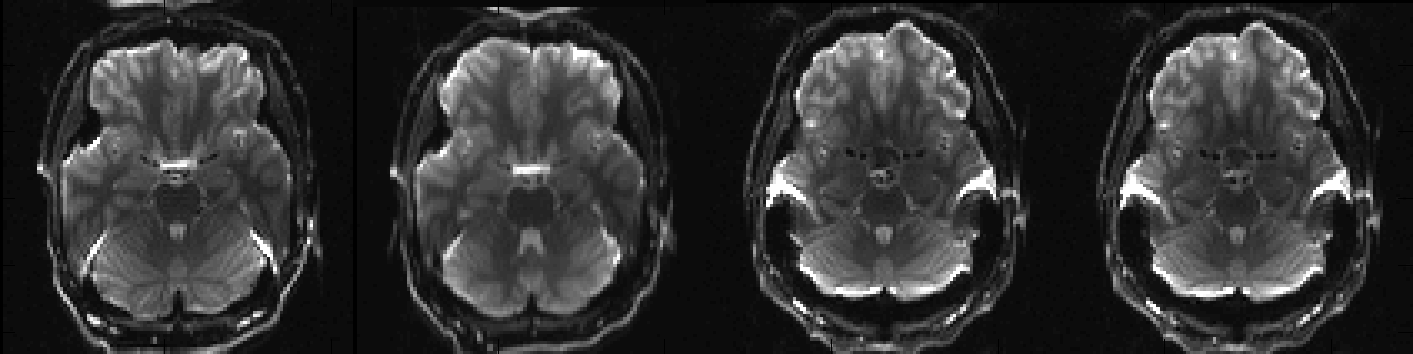

EPI images acquired with different PE-directions before correction

Above you can see a selected slice from the four volumes in an example file called my_b0_images.nii.gz. It is immediately obvious that the distortions in the first two images are vastly different from those in the two last images. If we take a look at the associated acqparams.txt file

we can see why. The two first images have been acquired with negative phase-encode blips in the y-direction, which means that signal from an area with "higher than expected" field (such as just above the ear-canals) will be displaced downwards. Conversely the two last images have been acquired with positive blips which means that signal from those same areas would be displaced upwards.

In addition to that we can see that the second image looks a little bit different to the first, despite having been acquired with identical parameters. This probably means that the subject moved between the acquisitions of the two images.